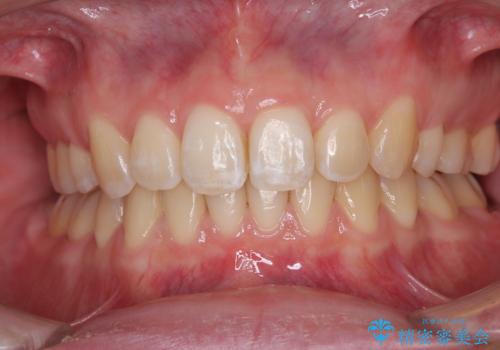

前歯が痛い!|歯の色が気になる!|精密根管治療後、オールセラミッククラウンで審美修復

担当医 河野豊嘉